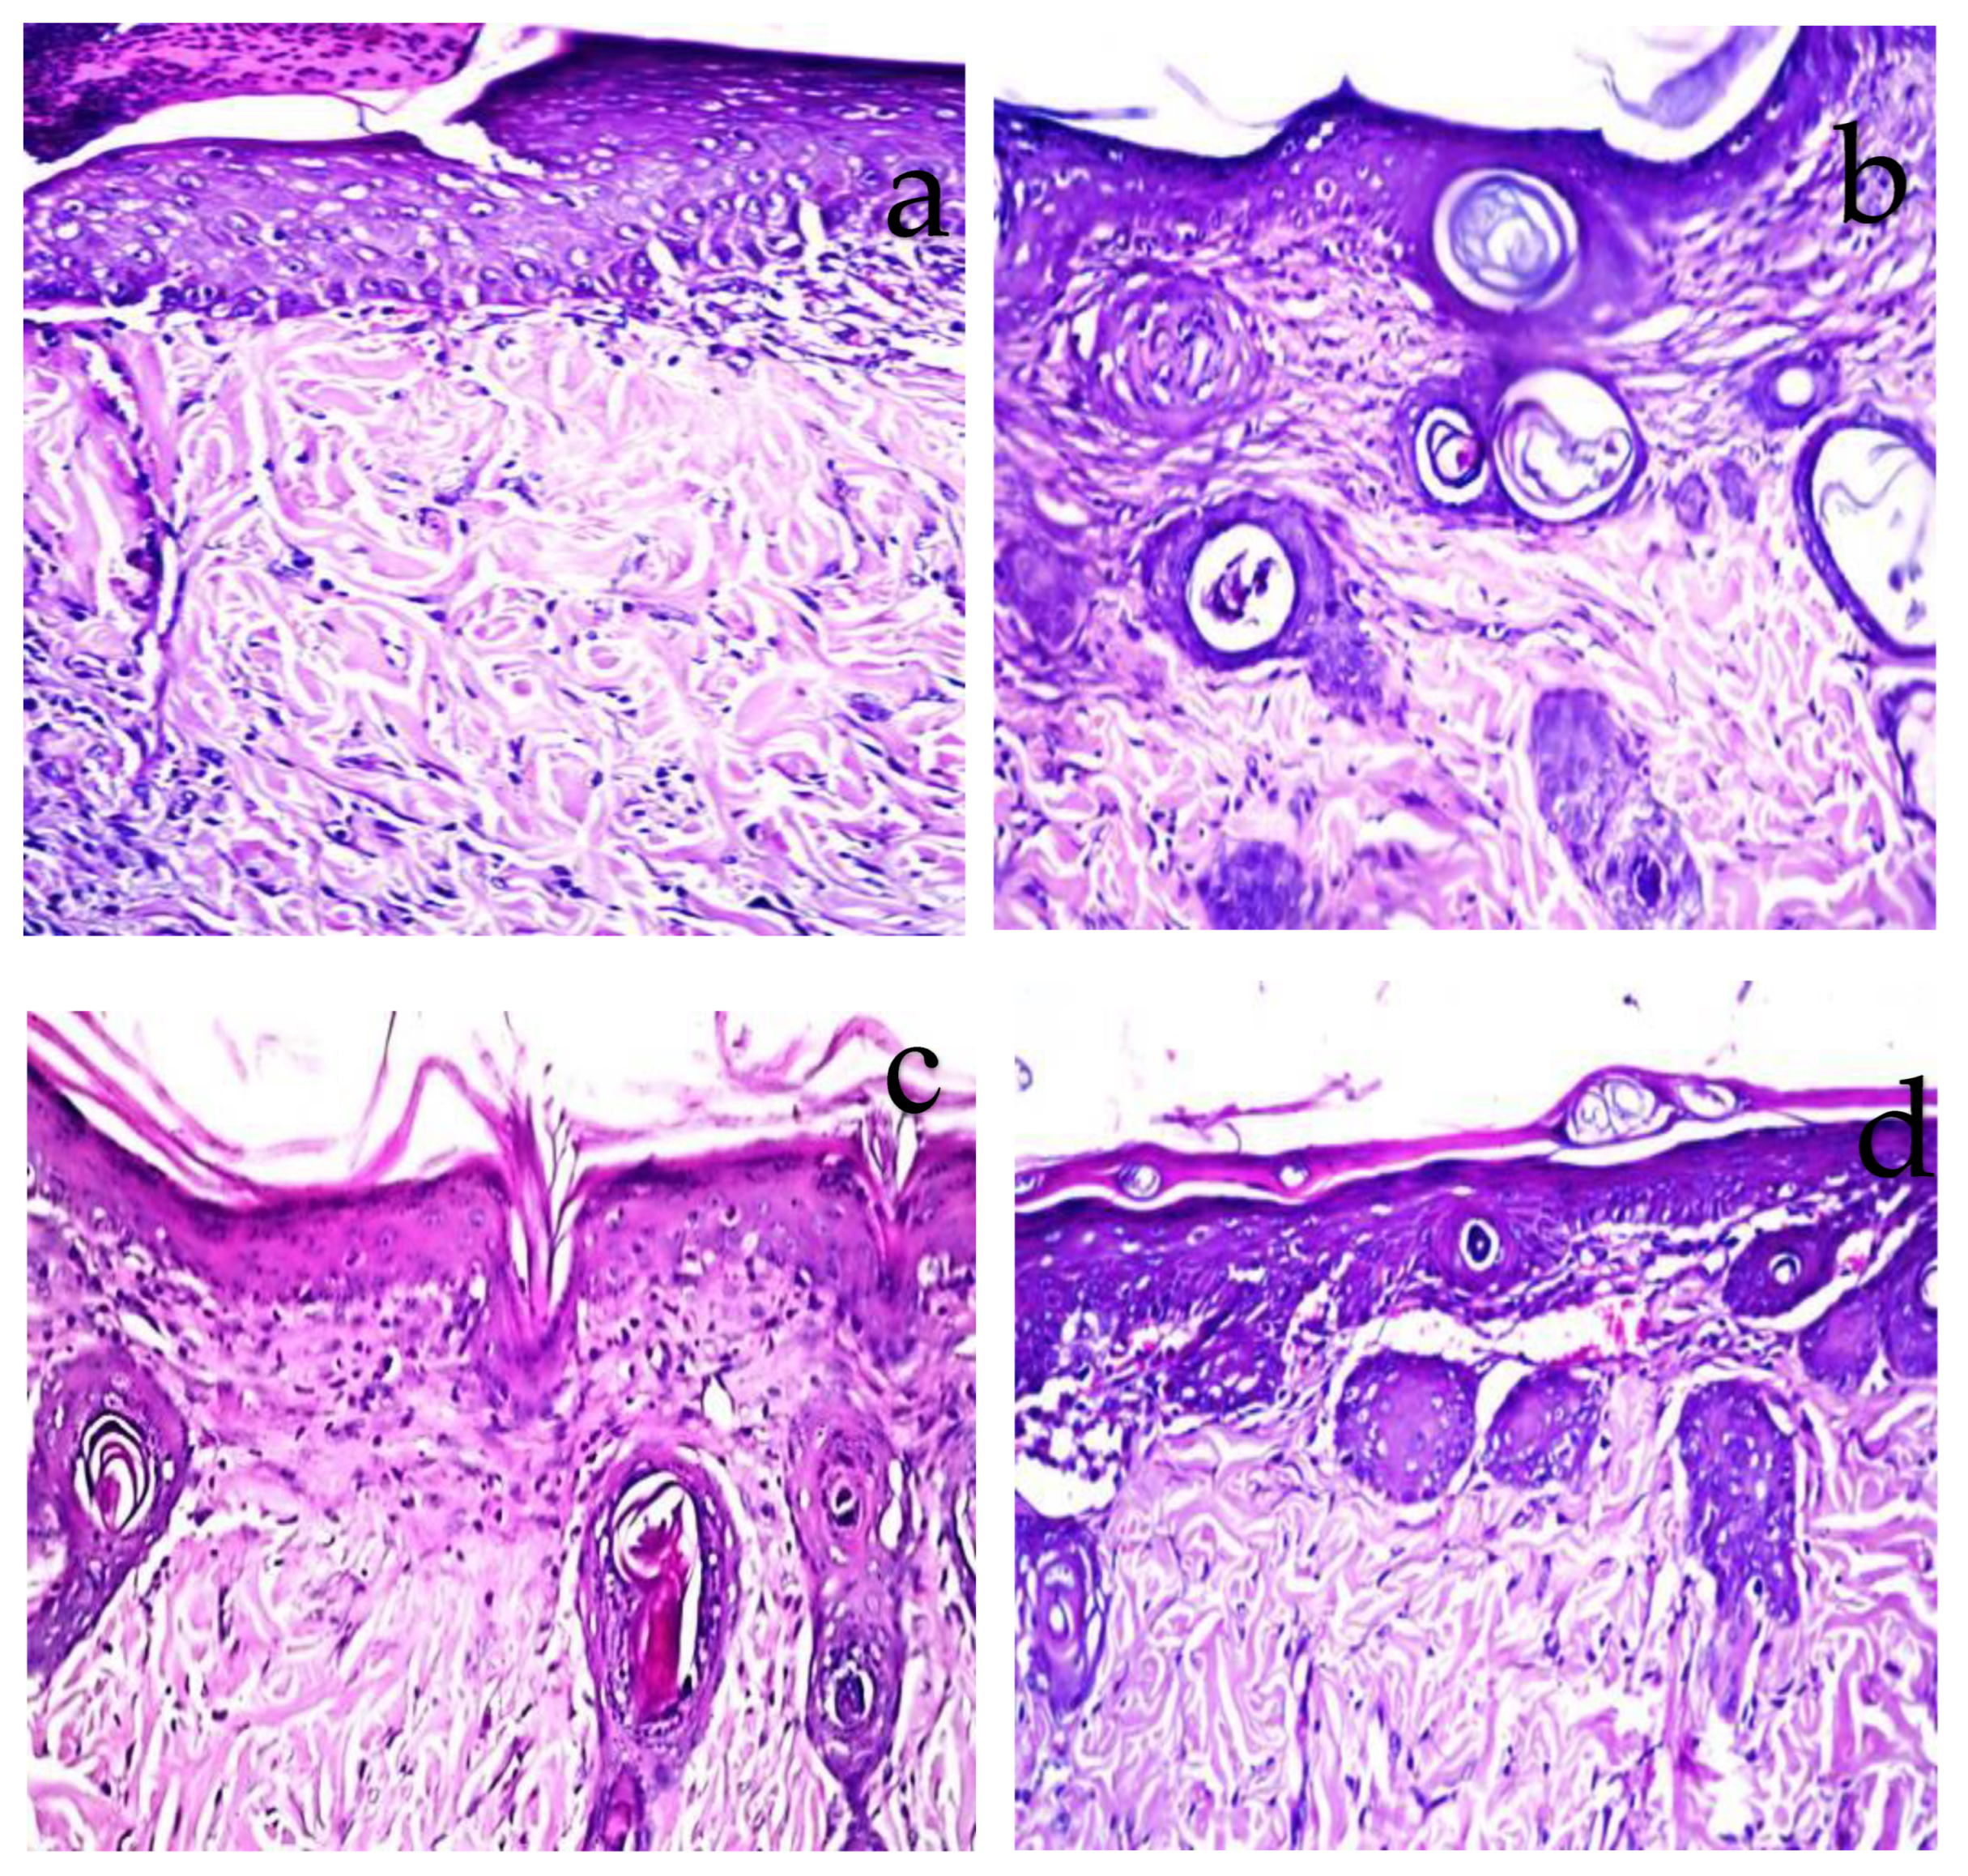

2.7. Histopathological Observations

Histopathological examination confirmed the visual observation and the calculated percentage of the burn area contraction. The burned areas treated with normal saline (negative control) showed acanthosis in the epidermis, while the underlying dermis showed granulation tissue formation and inflammatory cell infiltration with oedema (Figure 7a). When the burn was treated daily with TTO-loaded conventional gel, there was acanthosis in the epidermis associated with granulation tissue formation and few inflammatory cells’ infiltration in the dermis (Figure 7b). Whereas, for the burn area treated with the unmedicated nanolipogel, focal ulceration with acanthosis in the adjacent area was detected in the epidermis associated with granulation tissue formation and inflammatory cell infiltration in the underlying dermis (Figure 7c). The burn area treated with TTO-loaded nanolipogel showed a well-formed basal cell layer of the epidermis, as well as neovascularization and condensed dermal connective tissue beneath the basal cell layer, as seen without histopathological alteration (Figure 7d). The histopathological examination agreed with the results recorded by the semi-quantitative assessment of inflammatory infiltrate scored in the examined sections (Figure 8).

Figure 7.

Photomicrographs of treated rat skin compared to the negative control taken at magnification ×40. (a) Skin area treated with normal saline showing oedema with focal ulceration and adjacent acanthosis in the epidermis with underlying granulation tissue and inflammatory cell infiltration in the dermis. (b) Skin area treated with TTO-loaded conventional gel showing few inflammatory cells infiltration in the dermis. (c) Skin of rat treated with the unmedicated nanolipogel showing acanthosis in the epidermis associated with few inflammatory cells infiltration in the dermis. (d) Skin area treated with TTO-loaded nanolipogel showing normal histological structure.